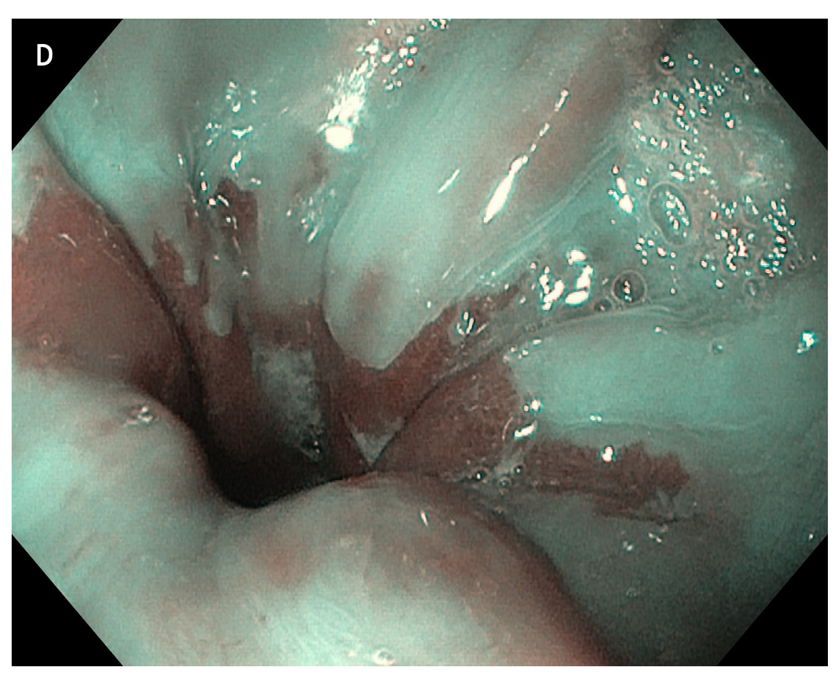

Figure 5 large areas of resected tissue and multiple lesions were independent predictors of stricture formation. A: Three areas of cervical inlet patches, with kissing distribution, in a middle age women with uterine cancer history, presenting for reflux complaints and globus sensation. Detailed image in (B) white light endoscopy and (C) narrow band imaging. D: Irregular Z line in the same patient suggesting concomitant gastroesophageal reflux disease.